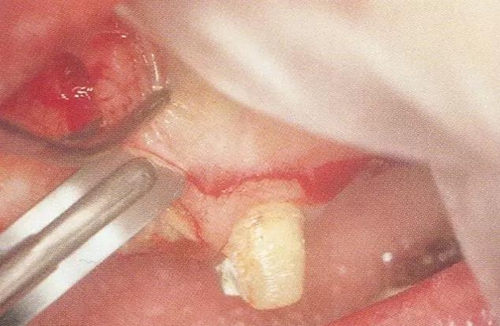

▼圖15-1  顯示牙齦翻瓣進行齦下刮治和根面平整的圖像。不良肉芽組織的去除和包含SC/RP在內(nèi)的清創(chuàng)處理決定了牙周外科處理結(jié)果是否良好。

18.jpg

▼圖15-2(左)  不良肉芽組織去除后出血變少

▼圖15-3(右)  在進行牙冠形成的牙齒上,可以用牙周外科用車針進行SC/RP,手術(shù)時間得以大幅縮短。

19.jpg